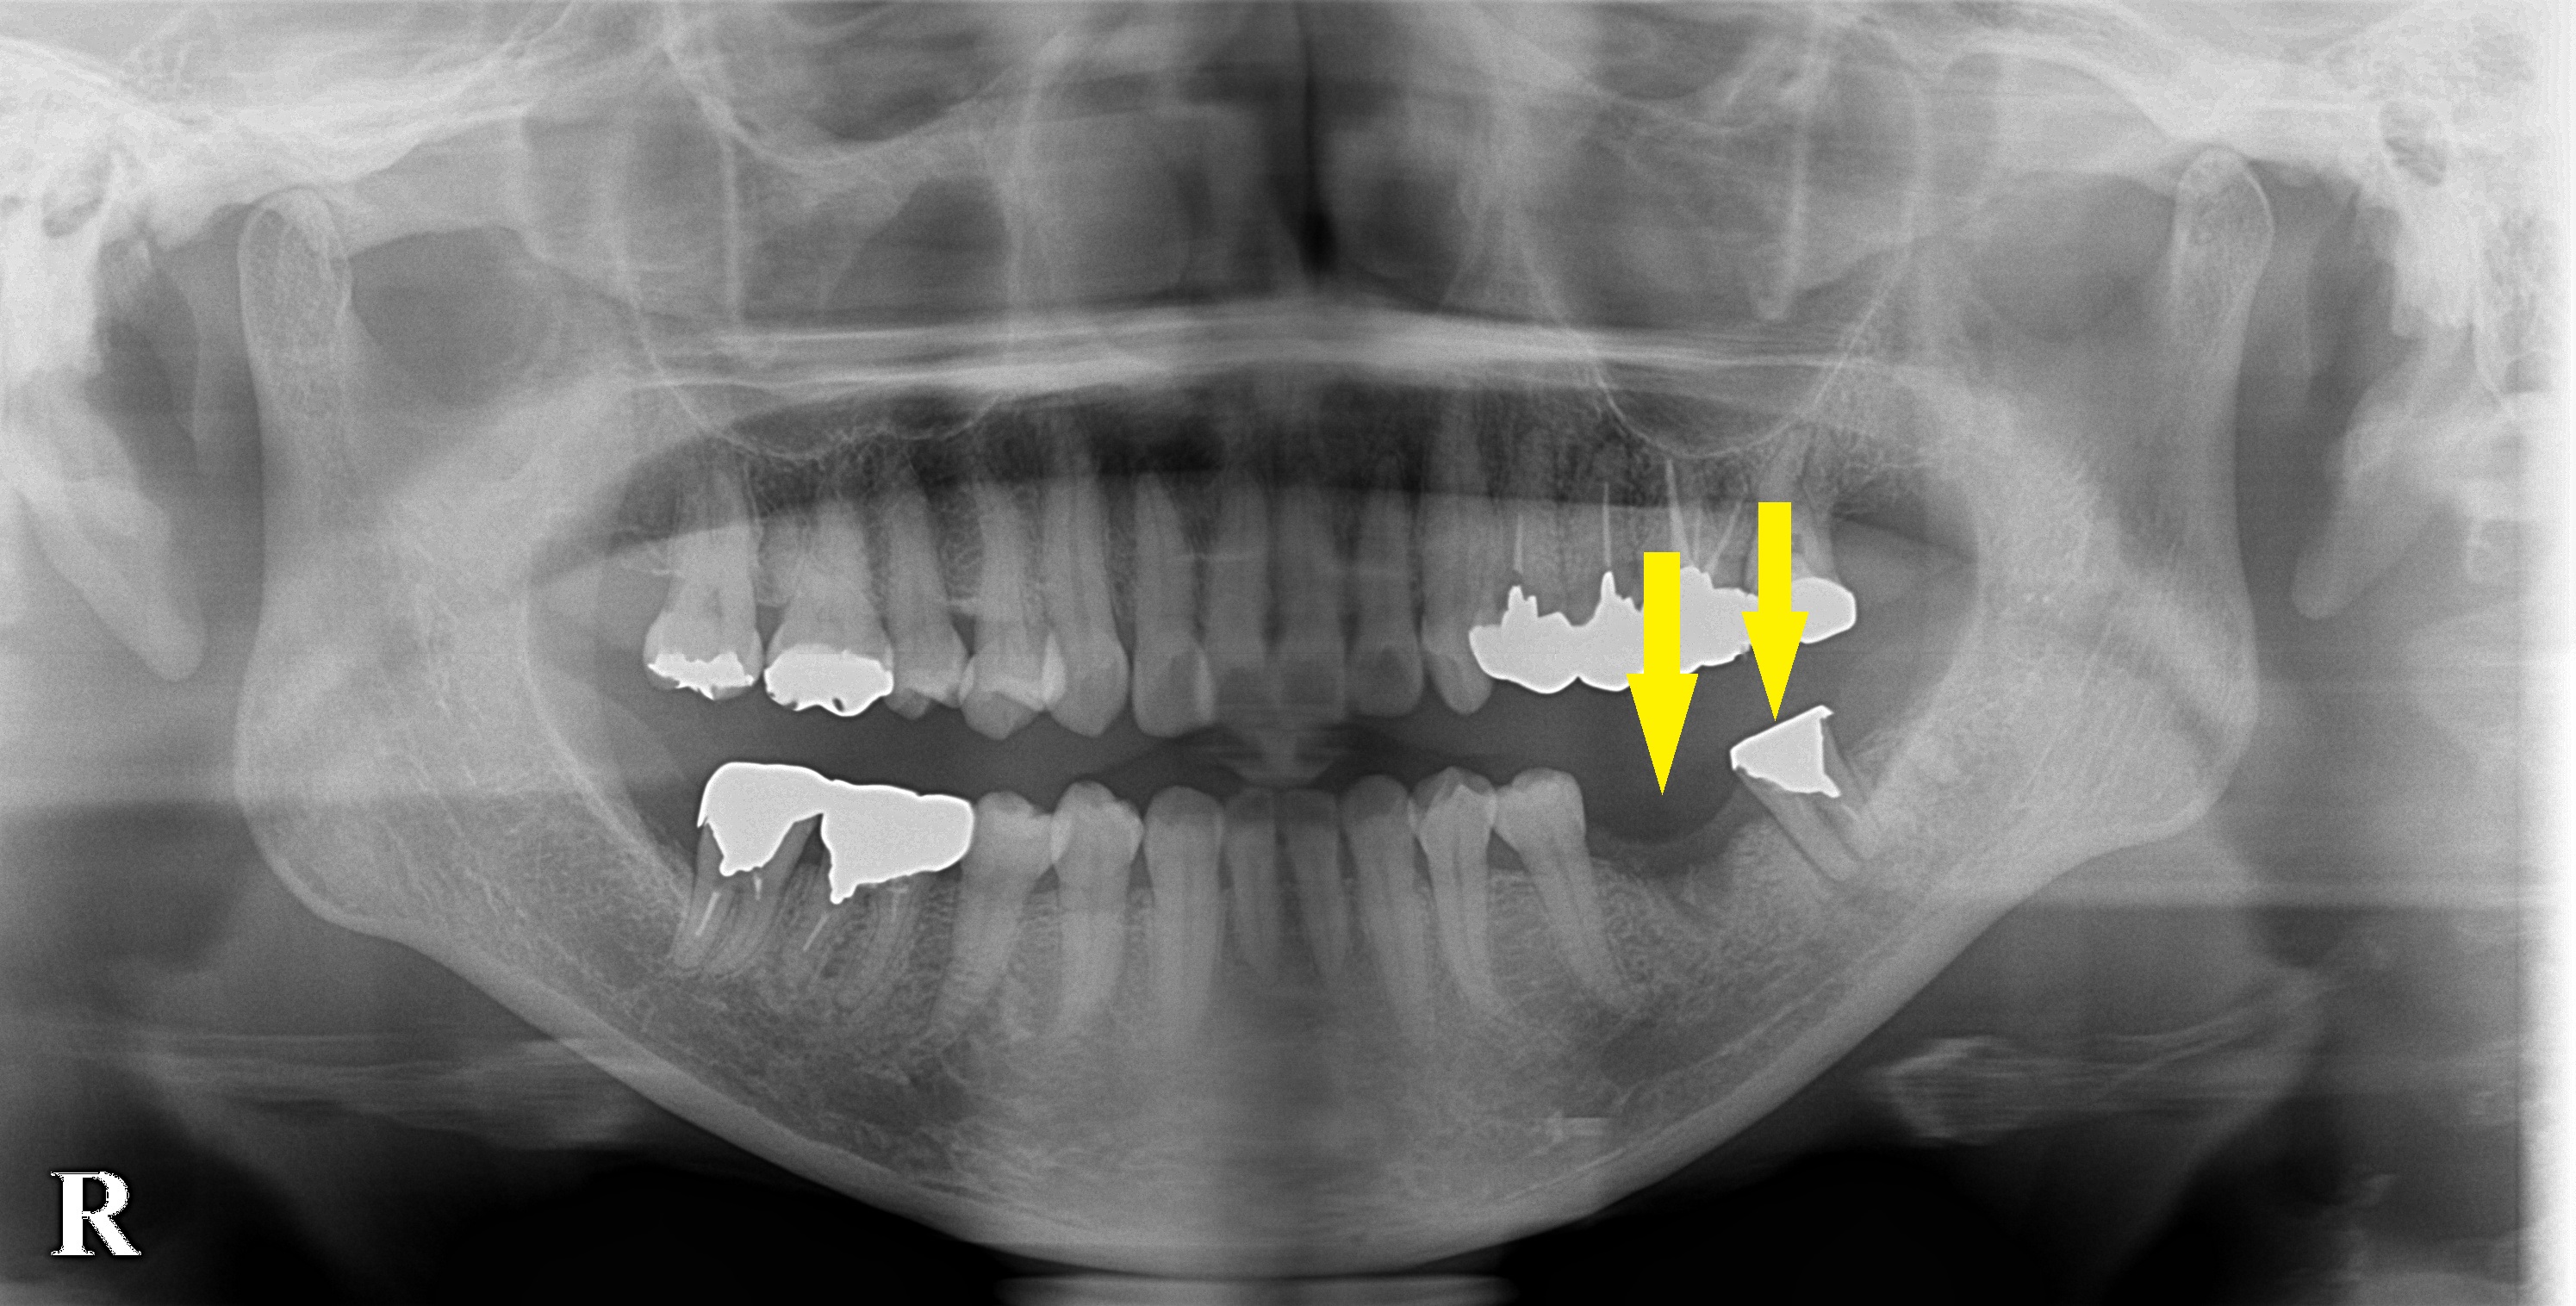

数か月前に抜歯した部位に、歯根のかけらのようなものが写っていましたので、抜歯とともにこの異物も摘出しました。

今回の場合は、異物を除去した部位が十分に治癒したのを確認してから、インプラント埋入を行うこととしましたので、抜歯後6か月ほど待っていただきました。